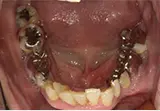

| 年齢/性別 | 50代女性 |

| 主訴 | 左下奥歯に痛みがある、全体的に治したい |

| 治療内容 | 全体的に歯周病やむし歯、根の治療を行い、仮歯を使用して咬合治療を実施。右下2本、左下1本の計3本を抜歯し、その後、右下に2本、左下に2本の計4本のインプラントを埋入しました。 |

| 治療期間 | 8か月 |

| 費用 | 2,106,500円税込 |

| リスク・副作用 | 炎症反応によって術後に腫れが生じることがあります。その程度は、手術の範囲や方法によって異なりますが、多くの場合、時間の経過とともに徐々に治まります。 ごく稀に、下顎奥歯の外科手術後に、唇や顎に痺れを感じることがあります。 |